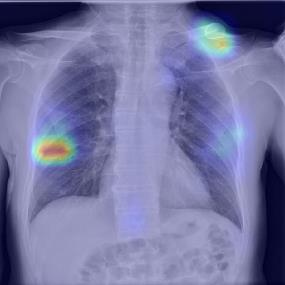

Chest X-ray (CXR) is the most typical diagnostic X-ray examination for screening various thoracic diseases. Automatically localizing lesions from CXR is promising for alleviating radiologists' reading burden. However, CXR datasets are often with massive image-level annotations and scarce lesion-level annotations, and more often, without annotations. Thus far, unifying different supervision granularities to develop thoracic disease detection algorithms has not been comprehensively addressed. In this paper, we present OXnet, the first deep omni-supervised thoracic disease detection network to our best knowledge that uses as much available supervision as possible for CXR diagnosis. We first introduce supervised learning via a one-stage detection model. Then, we inject a global classification head to the detection model and propose dual attention alignment to guide the global gradient to the local detection branch, which enables learning lesion detection from image-level annotations. We also impose intra-class compactness and inter-class separability with global prototype alignment to further enhance the global information learning. Moreover, we leverage a soft focal loss to distill the soft pseudo-labels of unlabeled data generated by a teacher model. Extensive experiments on a large-scale chest X-ray dataset show the proposed OXnet outperforms competitive methods with significant margins. Further, we investigate omni-supervision under various annotation granularities and corroborate OXnet is a promising choice to mitigate the plight of annotation shortage for medical image diagnosis.